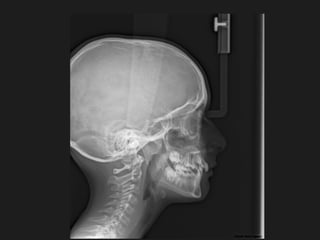

Panoramic (reconstructed from CT)

The most likely diagnosis for the facial asymmetry of this young girl is an

undiagnosed condylar fracture that most likely happen when she falled on a meta

crossbar bar ladder 2 or 3 years ago while she was 4 - 5 years old or so. The

condylar stump has healed and a new condylar head has formed, but the losted

substance of the condyle is gone. Therfore, the height of the ramus has

shortened.

The left ramus and condylar neck are shorter and the left eminence has no slope

if any. Healing and normal growth had reshaped both condyle and eminence.

!

Read more

When looking to the condyle from an anterior view, one can see the oblong

shape of a condyle but the left condyle is smaller.

The midline are not coincident. Note that the lower midline is toward right like

the occlusal plane canting to the right. This can be explained by the lack of

heigh of the left ramus and as normal growth occur, there is a wagon wheel

effect and the midline deviate toward the normal side, the occlusal plane is

moving up on the affected side.